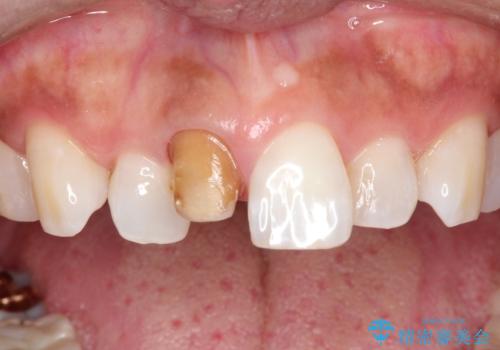

右上1は根管治療がされており、神経がないため歯自体も変色していること、詰め物の色も変色していることをふまえ、オールセラミッククラウン(スペシャル)による治療を行うことになりました。

根尖に病変はないこと、患者さんが根管治療は希望されなかったため、土台のやりかえからかぶせものまでを行っております。